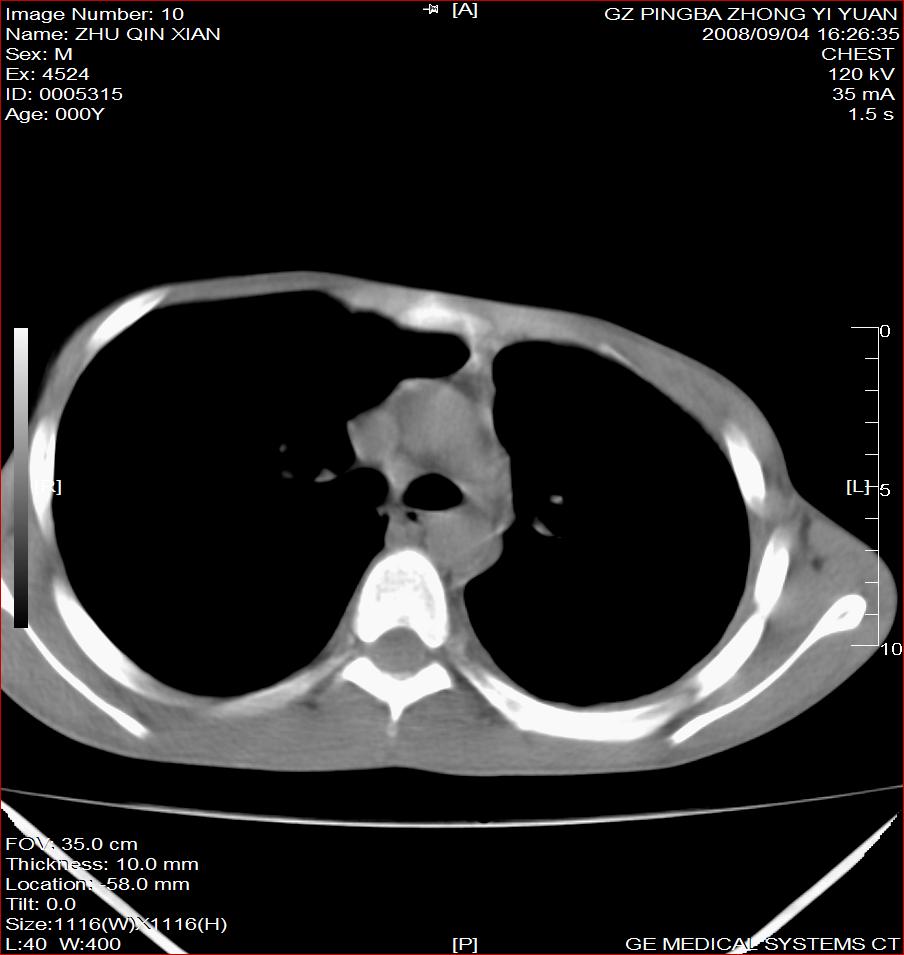

以下是引用随光逐影在2008-9-4 20:05:00的发言:[br]1)考虑两肺结核。2)左侧胸膜炎(胸膜肥厚、粘连,胸腔积液)。3)左侧局限性气胸。

以下是引用子十在2008-9-4 19:34:00的发言:[br]左上肺结核并空洞及双肺播散。节段性肺不张、胸腔积液、胸膜肥厚粘连。[br]